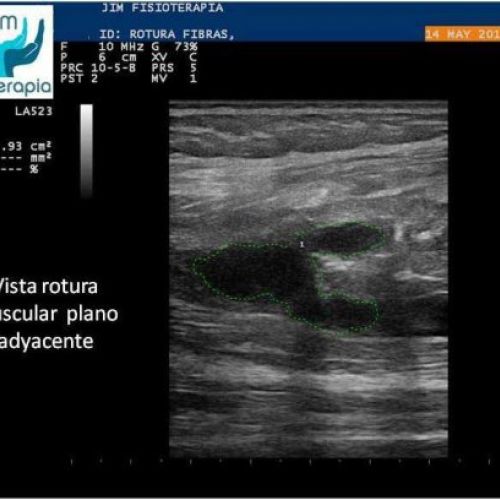

Tratamiento de rotura muscular con EPI®

Terapia de EPI® para el tratamiento de rotura muscular. Caso clínico de JIM Fisioterapia.